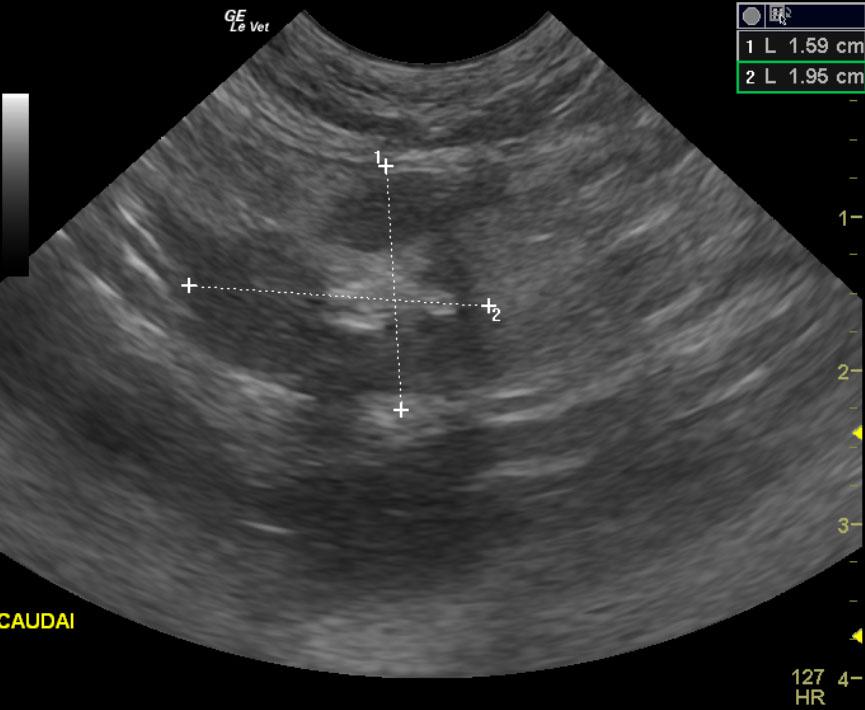

The patient is a feline DSH, MN, 8 year old. Concern for abdominal tumor due to decrease in appetite. Blood work is wnl. Urine specific gravity 1.045.